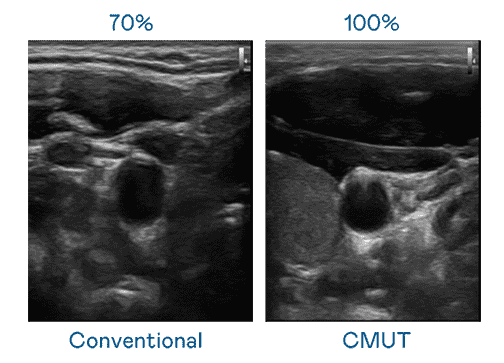

CMUT 技术是一种用电容式微机电元件来产生超音波讯号的技术。。与传统 PZT 压电式技术相比,,CMUT 频宽增加 30%,,,,更宽频的超音波讯号让影像解析度大幅提升,,,,是实现高影像品质医疗超音波扫描、、、、促进精准医疗发展的关键技术。。。。

超音波影像的解析度高低,,,首先取决于探头能发出的讯号频宽。。。。壹号平台 CMUT 可提供高清晰的超音波讯号,,提供高频宽、、、、高灵敏度、、、、影像纹理细节更高的超音波影像,,,协助医护人员缩短影像判读时间及利用精准的医疗影像进行诊断。。。。